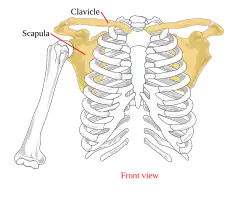

3D image Pectoral girdle—front

Pectoral girdle—front Diagram of the human shoulder joint, front view